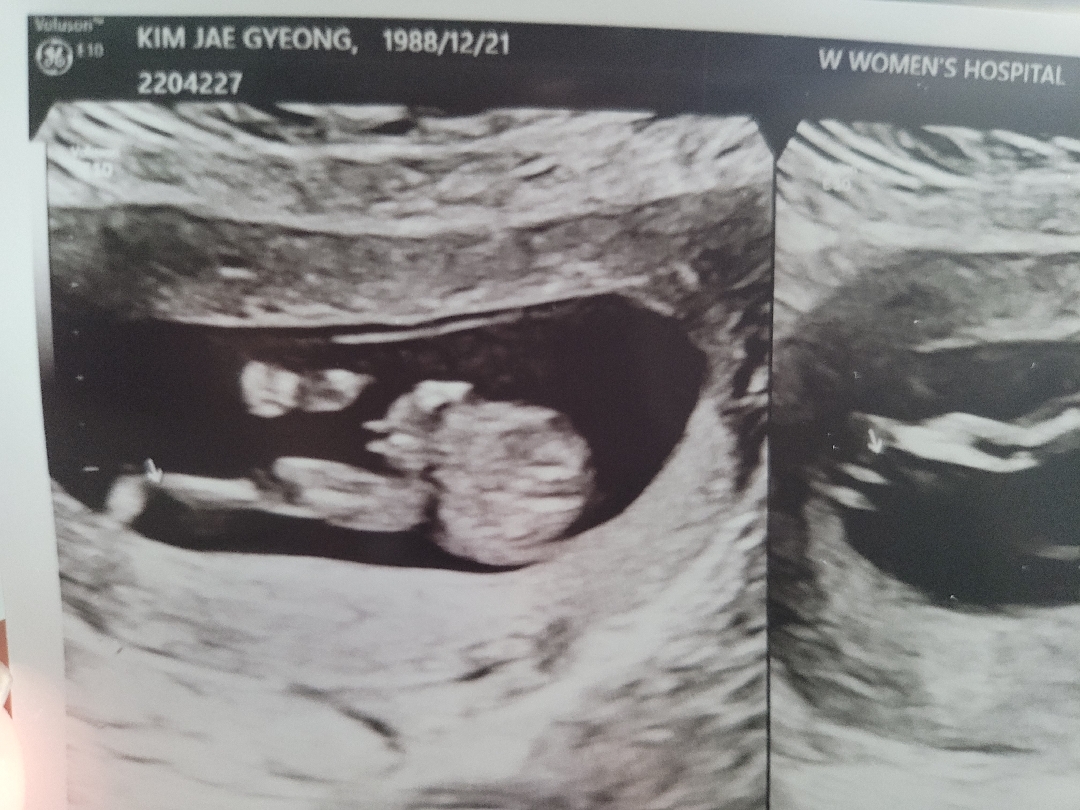

미사일같은데 딸같데요ㅋㅋㅋ

이게맞나싶고..ㅋㅋ 아직 시간이 더 있지만ㅋㅋ 딸이던 아들이던 다 좋은데 궁금한건 쩔수없나봐요........ 성별테스트도 해외직구로 산지 한달이되도 안오고.... 맘님들눈엔 뭐로보이나요......^^

몇주신가용 ?!?

13주용^^

아들 같긴 하네용 ㅎ ㅎ

무적권 아들